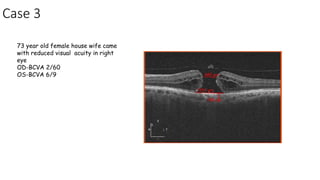

Case 3

73 year old female house wife came

with reduced visual acuity in right

eye

OD-BCVA 2/60

OS-BCVA 6/9